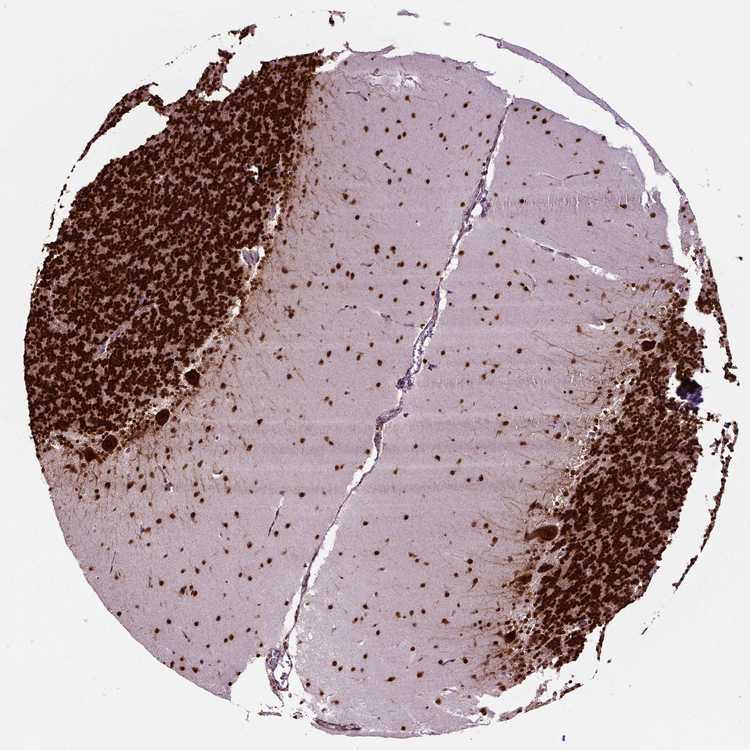

BRAIN CEREBELLUM Show tissue menu

CEREBELLUM - Expression summary

Cells in granular layer: High

Cells in molecular layer: High

Purkinje cells: High

CEREBELLUM - Antibody stainingi

Antibody staining in the annotated cell types in the current human tissue is reported as not detected, low, medium, or high, based on conventional immunohistochemistry profiling in selected tissues. This score is based on the combination of the staining intensity and fraction of stained cells.

Each image is clickable and will lead to virtual microscopy that enables deeper exploration of all samples and also displays staining intensity scores, fraction scores and subcellular localization as well as patient and tissue information for each sample.

Antibody CAB016114Antibody CAB069989

Purkinje cells HighHigh

Cells in granular layer HighHigh

Cells in molecular layer HighHigh